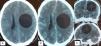

En la actualidad la hidatidosis es una parasitosis accidental, siendo su ubicación cerebral rara. Presentamos el caso de un varón de 33años que llega a emergencias por síndrome de hipertensión endocraneana y focalización derecha. La tomografía computarizada mostró una lesión quística frontoparietal izquierda, la cual es intervenida quirúrgicamente, realizándose la exéresis completa de la lesión con buena evolución posterior. La hidatidosis es una patología poco frecuente a nivel cerebral, por lo que es importante la sospecha clínica para orientar los estudios al diagnóstico precoz. Revisamos la patogenia, el diagnóstico y el tratamiento de la hidatidosis cerebral.

Hydatid disease is an accidental parasitosis, with brain location being rare. The case is reported of a 33year-old male, with no history of note, who was admitted to hospital with intracranial hypertension syndrome and right hemiparesis. Computed tomography showed a cystic lesion in the left frontal-parietal lobule. Surgery was performed by complete excision of the lesion, with a good outcome. Hydatid disease is a rare condition in the brain. Clinical suspicion is important for an early diagnosis. A review is presented on the pathogenesis, diagnosis and treatment of cerebral hydatid disease.